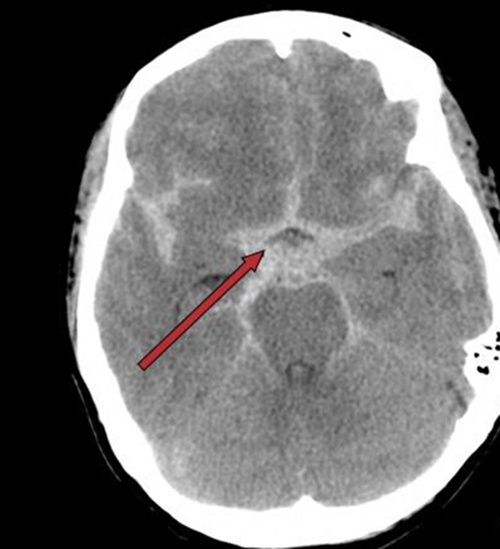

送进医院的时候,患者的病情已经相当严重,她两侧的瞳孔已经不等大,而且对光反射很弱!立刻完善了头颅CT等检查,结果却是蛛网膜下腔出血!

直到现在,这位被同事认为只是偏头痛的患者已经住在重症监护病房里,虽然花费了很多费用,但是依旧生死未卜!